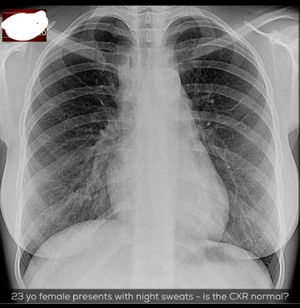

Now Xray First of all AP window this window is between aortic arch and pulmonary trunk so normally it is conacave bt see here its concavity is lost so we can say there may be some mass or lymphnodes enlargement now see here extra medistinal contour it is little bit up to the ap window and there is anything also increased paratracheal density which is not that much important but in this case it s important this paratracheal density indicate some problem to paratracheal lymph nodes.... So at this point according to all the findings its not obviously tb or metastatic tumor and it s also not sarcoidosis bcs bilateral hilar symmetrical lymphadenopathy is not seen so the most probable diagnosis should be lymphoma..... So now for further diagnosis we have to take biopsy from lymph nodes now here radiology plays a big part in selecting the right place to take sample So after diagnosis we find it is hodking s lymphoma.... But by xray we can diagnose till lymphoma for hodking s lymphoma we have to take biopsy...